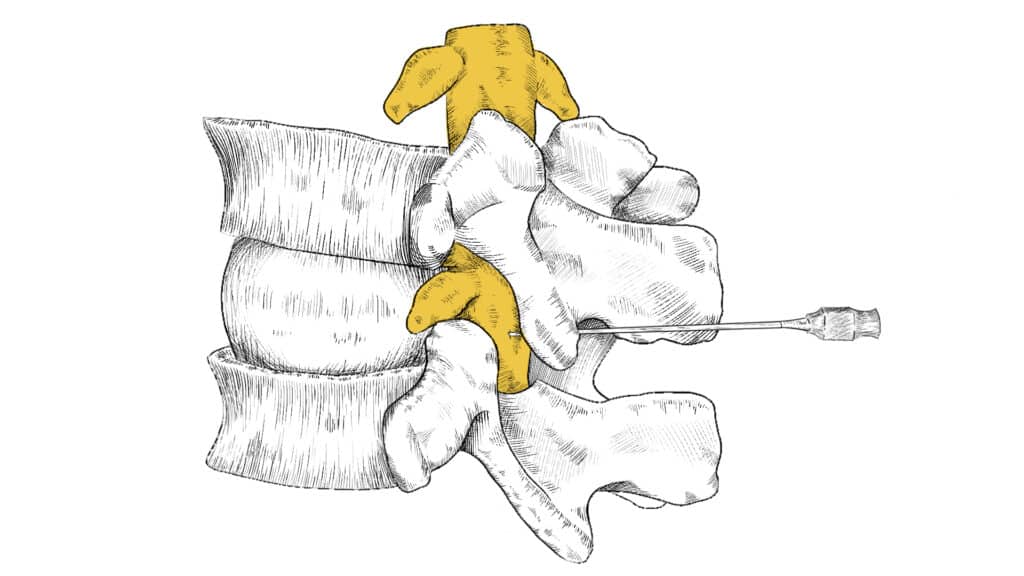

Podanie leku do przestrzeni nadtwardówkowej jest wykonywane przez lekarza specjalistę (najczęściej anestezjologa lub neurochirurga) w warunkach ambulatoryjnych (pacjent wraca do domu tego samego dnia). Zabieg polega na wprowadzeniu igły do przestrzeni nadtwardówkowej pod kontrolą RTG (fluoroskopii), co zapewnia precyzyjne dotarcie do celu. Następnie podawany jest lek, którym najczęściej jest mieszanina kortykosteroidu (działanie przeciwzapalne) i środka znieczulającego miejscowo.